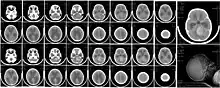

Scanner du cerveau d'une fillette de 6 ans atteinte d'un médulloblastome (tumeur cérébrale la plus fréquente chez les enfants de moins de 2 ans).

Le médulloblastome est un cancer qui apparaît (souvent avant la puberté) dans la moelle épinière à la base du cerveau, dans le cervelet ou la partie arrière du cerveau ; c'est le plus courant des cancers du cerveau de l'enfant[4].